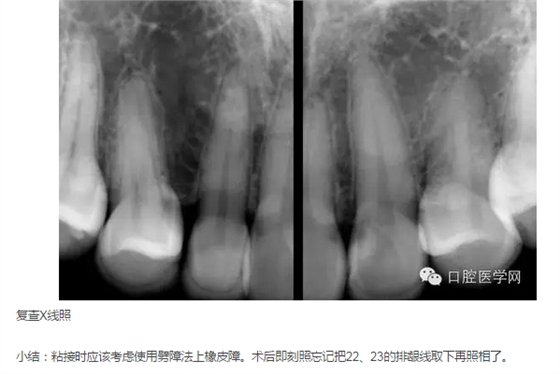

來源于口腔醫(yī)學(xué)網(wǎng)